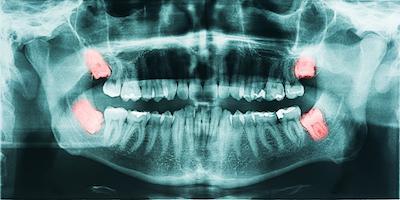

Dental x-ray showing wisdom teethPeriodic dental x-rays allow our dentist to see below the surfaces of your teeth. Decay can hide underneath your enamel or just below the gumline, making it impossible to detect with just a visual dental exam.

• Panoramic x-rays – takes a comprehensive image of all of your teeth at once and includes your jaw joints, bone, and dental anatomy (every 3 to 5 years)